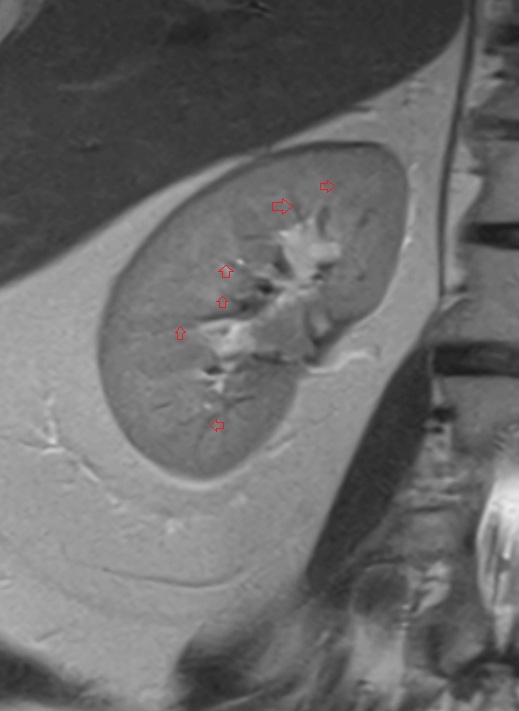

- kidneys

- Right kidney

- Left kidney

- Kidney cortex (Renal cortex)

- Renal capsule

- Renal medulla

- Renal pyramids

- Renal pelvis

- Renal artery

- Renal vein